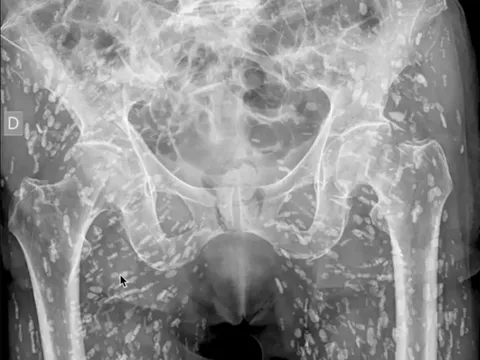

Hình ảnh X-quang của bệnh nhân nhiễm hàng trăm trứng sán lợn khiến người xem rùng mình

Một bác sĩ cấp cứu gần đây đã chia sẻ một hình ảnh X-quang mà anh cho là "khó tin nhất" trong sự nghiệp của mình, khi cơ thể một bệnh nhân đầy trứng sán lợn mắc kẹt trong các mô mềm.